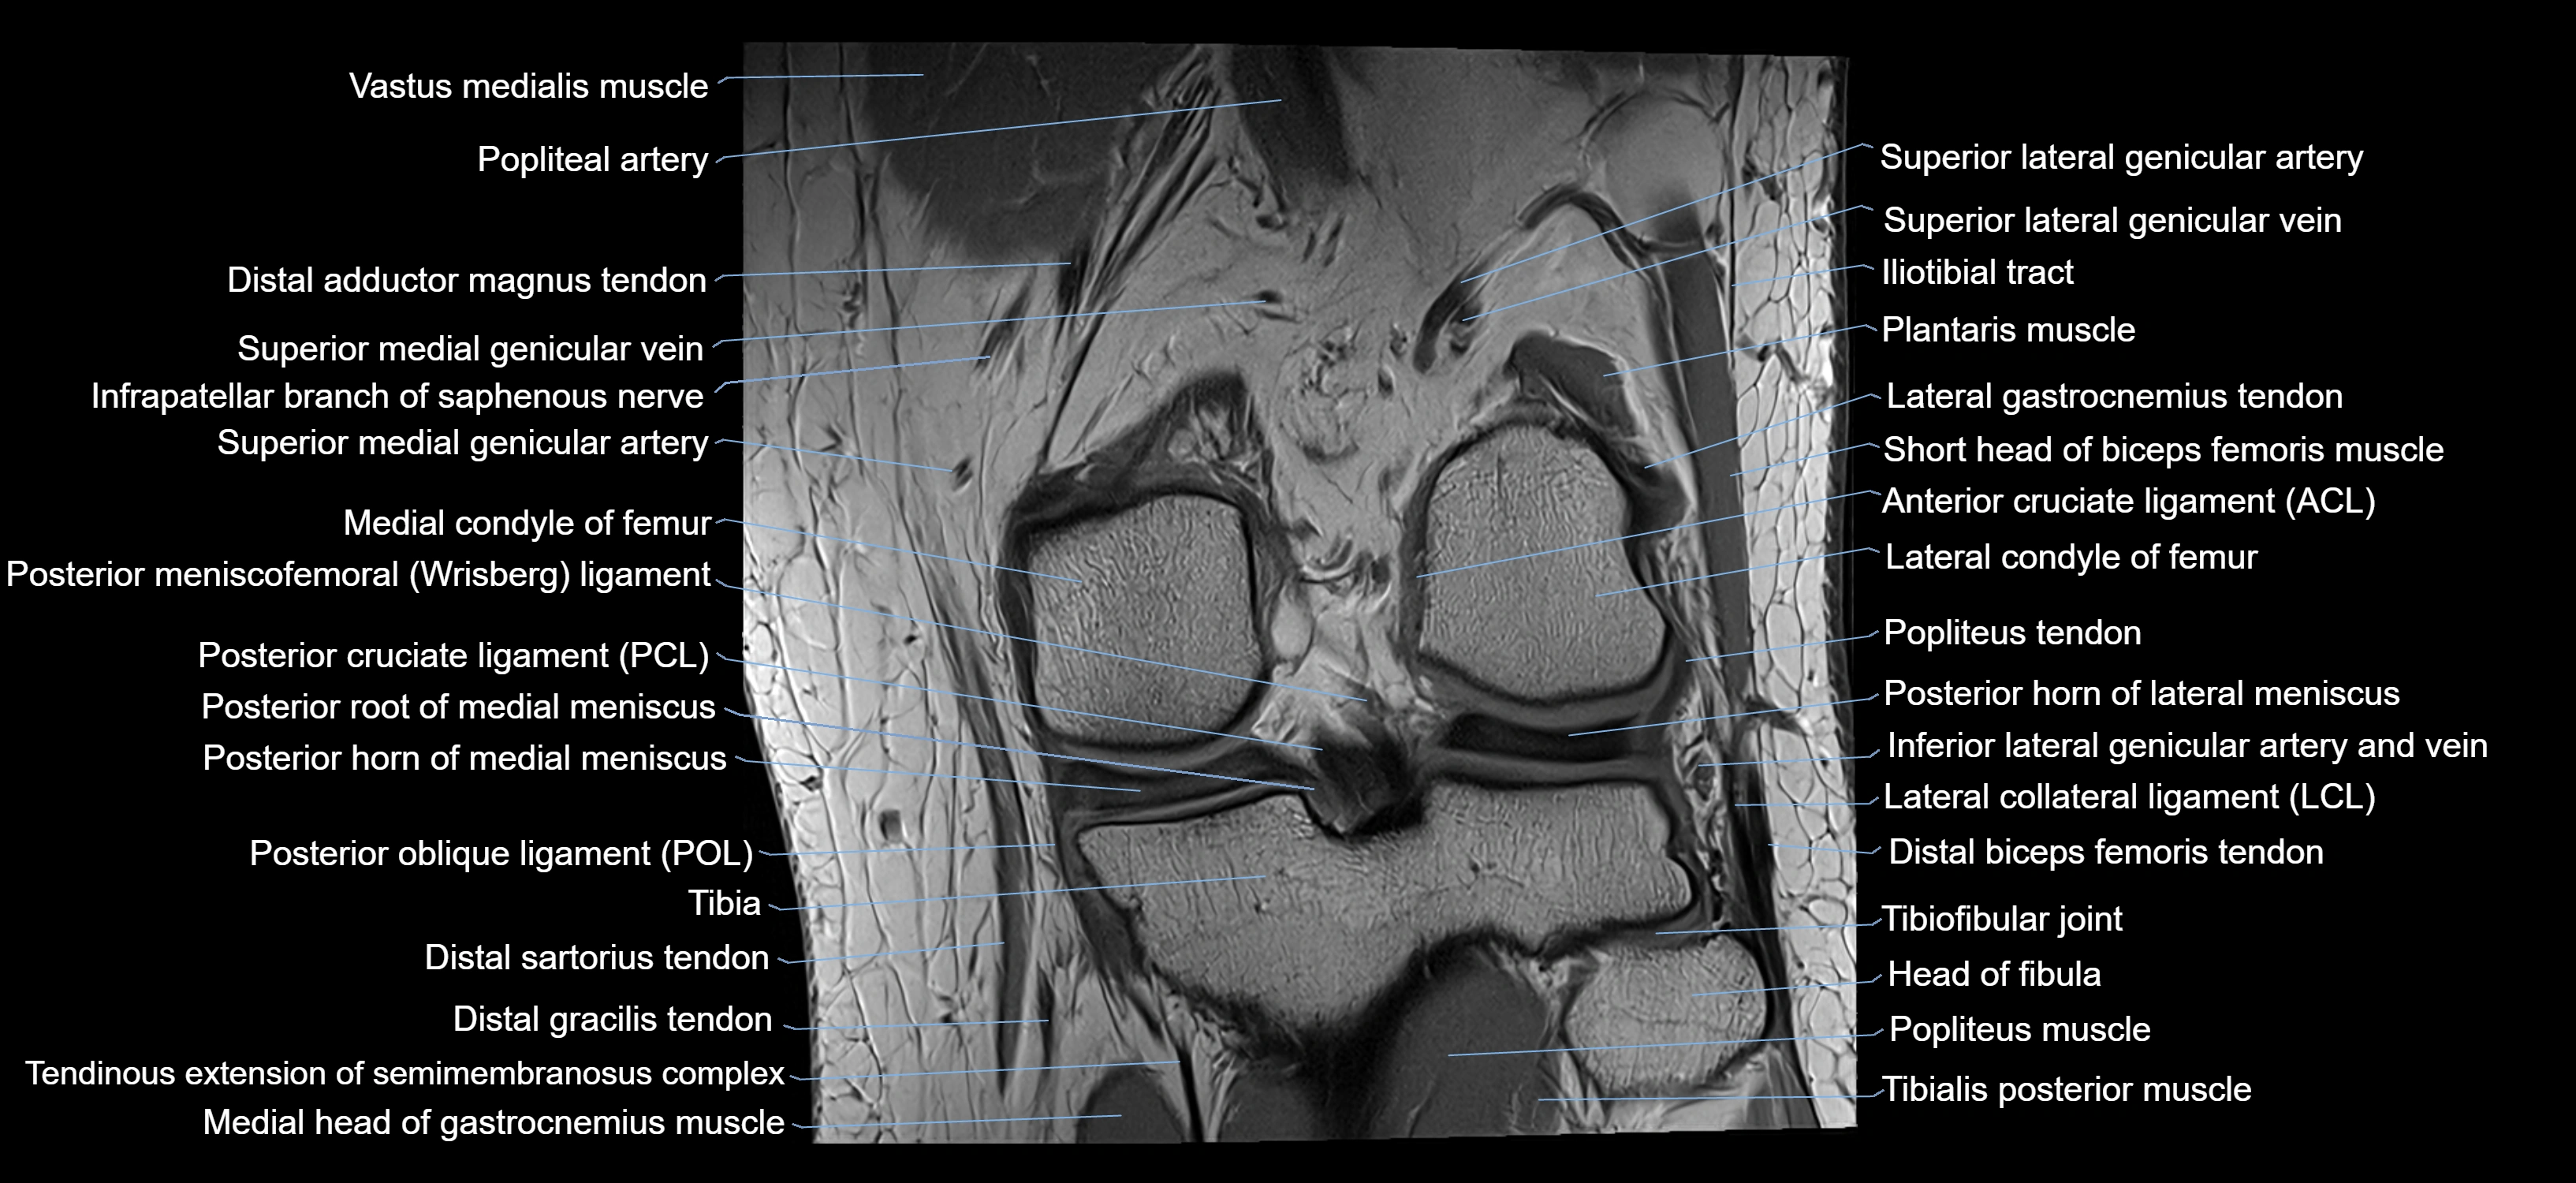

- Knee Joint

- Medial condyle of femur

- Lateral condyle of femur

- Posterior cruciate ligament

- Posterior horn of lateral meniscus

- Posterior horn of medial meniscus

- Posterior meniscofemoral ligament

- Posterior root of medial meniscus

- Popliteus tendon

- Popliteus muscle

- Popliteal artery

- Superior lateral genicular artery

- Superior lateral genicular vein

- Superior medial genicular artery

- Superior medial genicular vein

- Lateral collateral ligament

- Lateral gastrocnemius tendon

- Lateral head of gastrocnemius muscle

- Medial head of gastrocnemius muscle